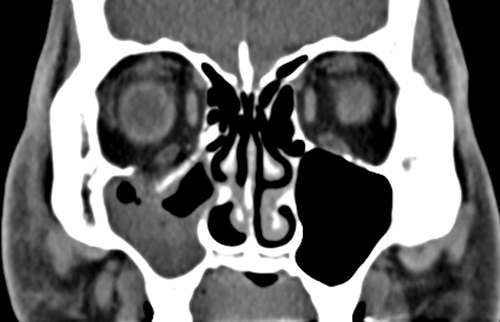

CT of the orbit and midface (axial, coronal, and parasagittal views, 1- to 1.5-mm sections, without contrast) is obtained in all cases of suspected orbital fractures. Bone windows are especially helpful in fracture evaluation (See Figures 3.19.2 and 3.19.3), including the narrow, often-missed white-eyed blowout fracture (WEBOF). Inclusion of the midfacial skeleton is mandatory to rule out zygomatic complex or other midfacial fractures. If there is any history of loss of consciousness, brain imaging is recommended.